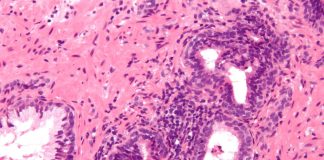

Fibromul uterin

Fibromul uterin reprezinta o masa celulara care se dezvolta la nivelul uterului. Acesta poate aparea la exteriorul uterului, in interiorul cavitatii uterine sau chiar...